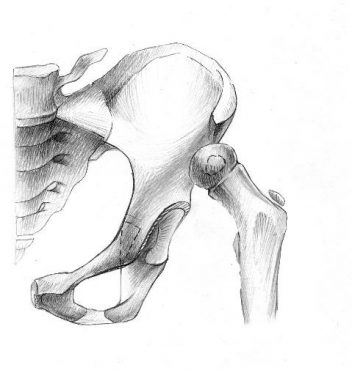

2. Открытое вправление бедра в сочетании с транспозицией вертлужной впадины (подвздошной остеотомией таза)

Применяется у детей старше 1 года в тех ситуациях, когда врожденный вывих бедра сочетается с выраженным недоразвитием вертлужной впадины.

Разработанная нами методика подвздошной остеотомии не требует использования трансплантата. То есть, при фиксации фрагментов остеотомии тазовой кости нет необходимости в использовании чужеродных тканей или заборе собственного костного трансплантата.

«Способ хирургического лечения детей с патологией тазобедренного сустава» (патент РФ на изобретение № 2405486 от 10.12.2010 г.)